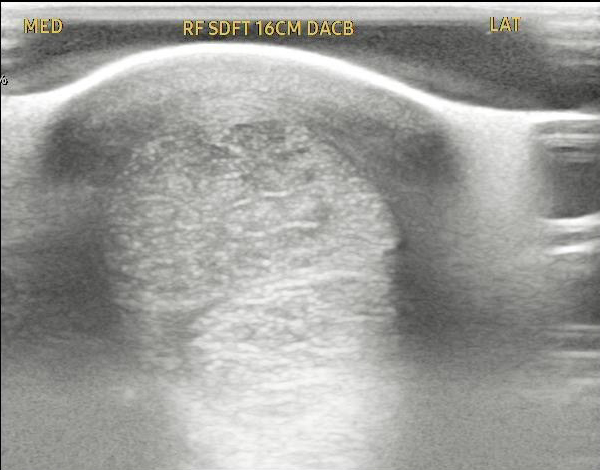

Case Study 2 – Equine Tendon Regeneration

The attached images show a pre- and post-treatment equine superficial digital flexor tendon injury.

This horse received two injections spaced one month apart and at the 2 ½ month point has produced a reduction in the core tendon lesion of approximately 70%.

Source: Temecula Creek Equine